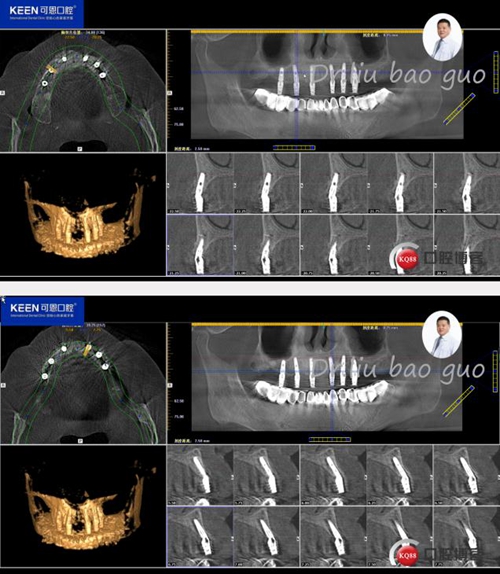

手術(shù)前種植軟件設(shè)計(jì)方案

術(shù)后照片